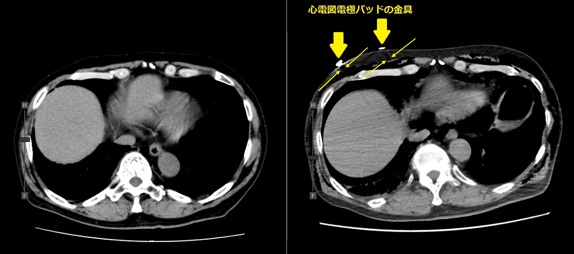

撮影部位に金属類がついた状態で撮影を行うとアーチファクトと呼ばれる障害陰影が画像上に現れてしまい,診断の妨げになってしまいます。そのため頭・頚部の検査ではヘアピン,ピアス,義歯などははずしていただきます。また,胸部や腹部等の検査ではブラジャーやファスナー,チャックなどが撮影時に写り込まないよう検査着に着替えてからの検査を推奨しています。

図1. 金属によってアーチファクトが写り込んでいるCT画像の例

金属類の周りに黒い帯状の筋のように見えるものが金属アーチファクトです。図2では黄色い矢印で挟まれた部分(→ ←)に現れています。